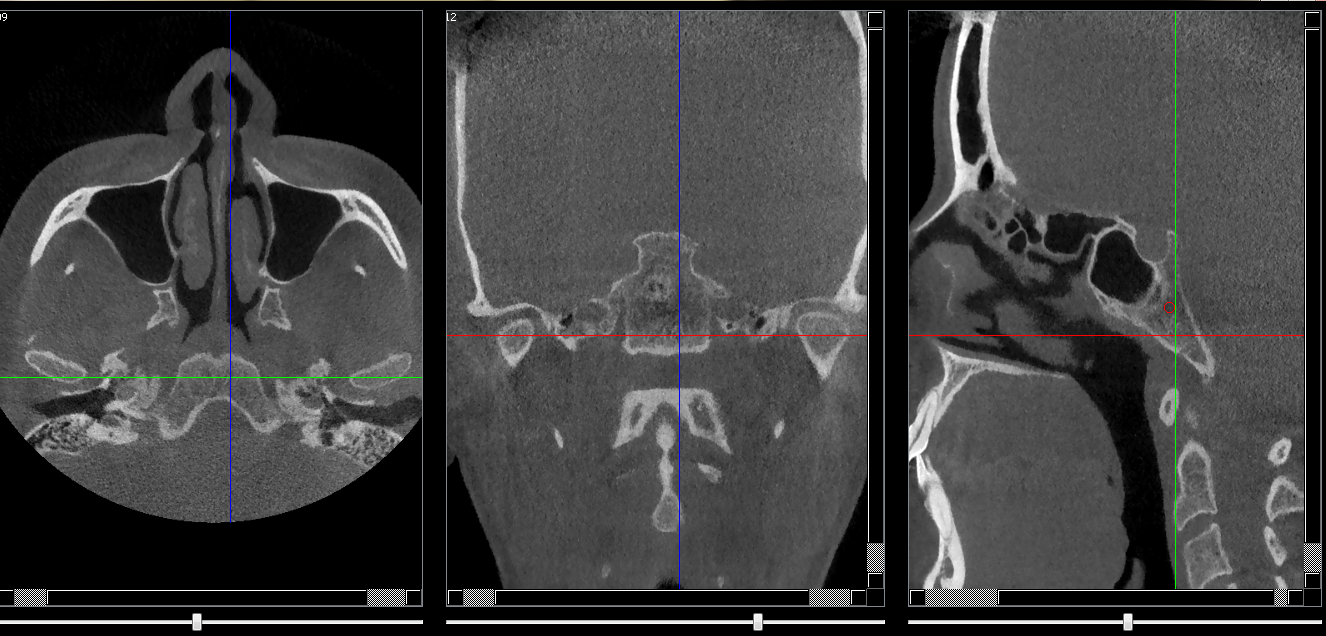

Structures osseuses

Clivus

Repères anatomiques

- Coupe transversale

- Début : Base des condyles

- Fin : Sinus sphénoide

- Coupe frontale

- Début : Sinus sphénoide

- Fin : Méat acoustique externe

- Coupe saggitale

- Début : Epine de l'os sphénoide droit

- Fin : Epine de l'os sphénoide gauche

Infos sur l'image

- Auteur : Pr Bourzgui

- Co-auteur : Dr Makoure

- Affiliation : Orthopédie dento-faciale

- Date production : 2019